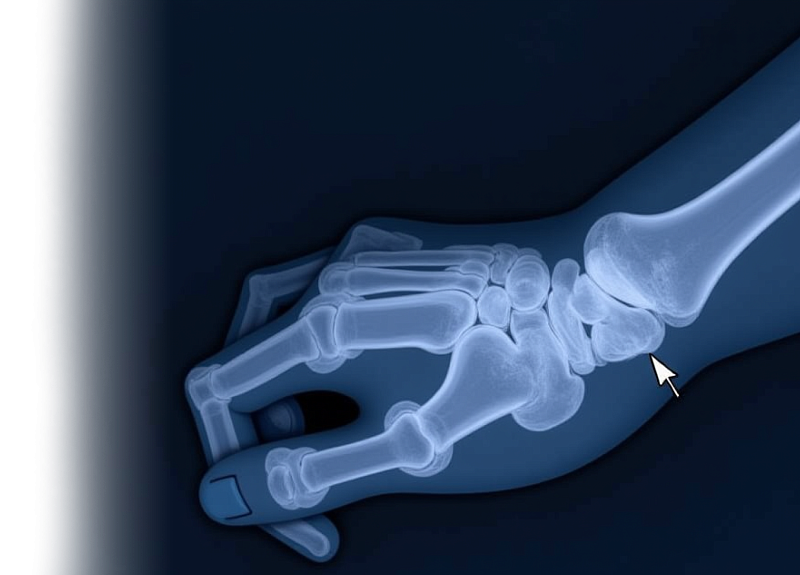

Компьютерная томография кисти – важный метод прицельного исследования состояния кисти. Это неинвазивное обследование, которое позволяет специалистам провести диагностику различных заболеваний и травм кисти.

Показания для проведения КТ кисти:

• травма, боль, отек кисти;

• подозрение на наличие опухолей или кист.

КТ позволяет исключить патологию кисти костно-травматологического, дегенеративного генеза, изменений, характерных для системного заболевания.